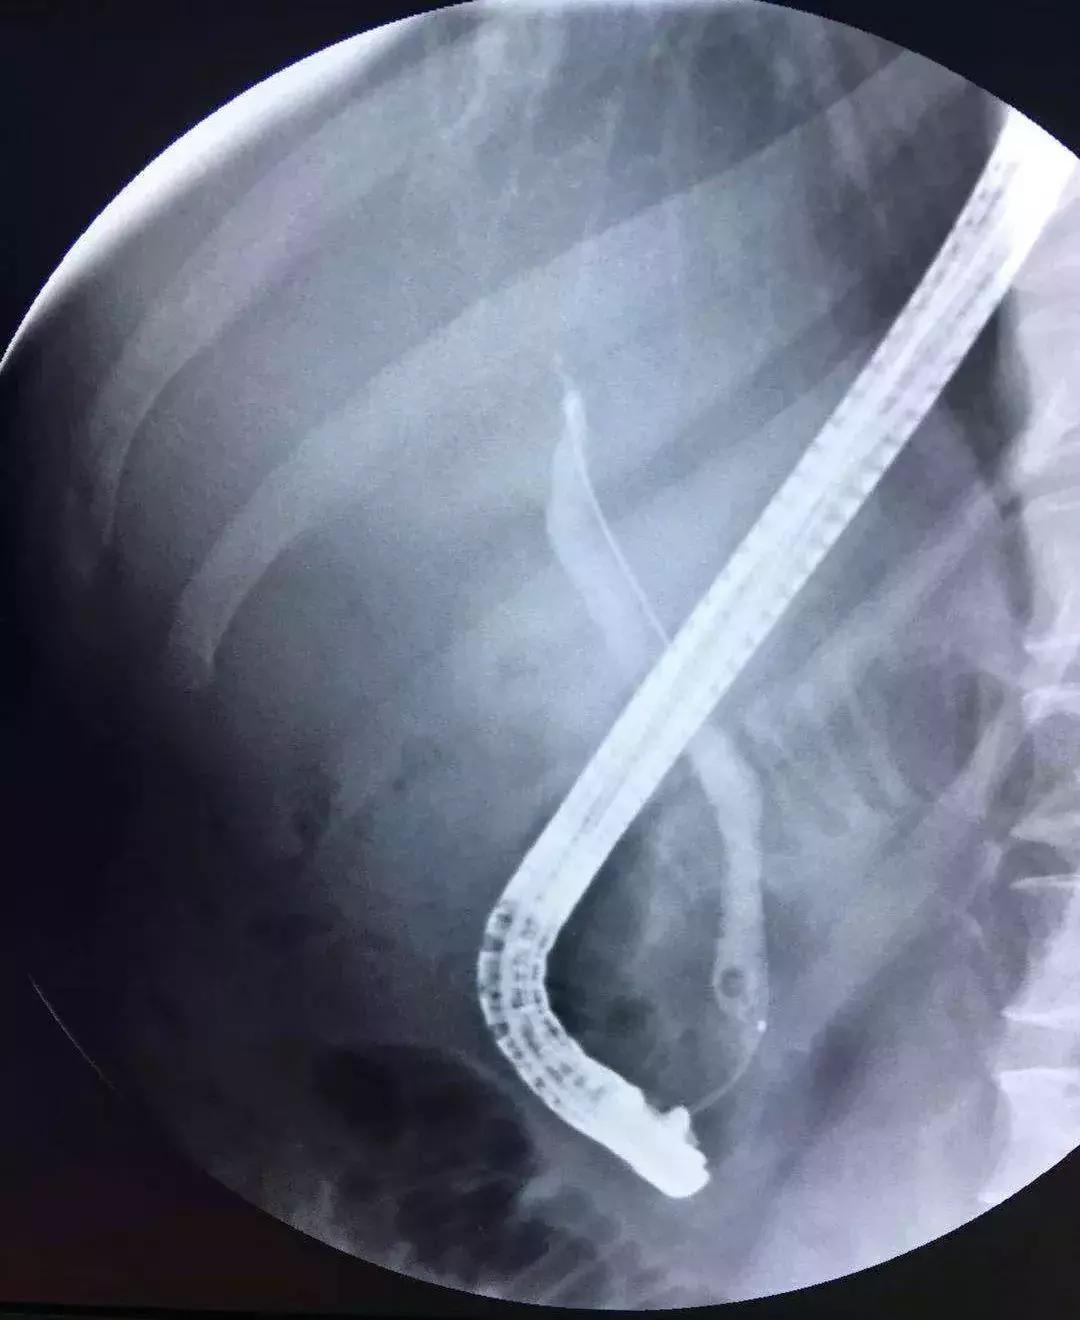

ERCP治疗

对于轻度或中度急性胆管炎伴胆管结石且无抗凝治疗或凝血功能异常的病人,可考虑在胆管引流的同时进行内镜下括约肌切开术(EST)清除结石,但EST常见的并发症有胰腺炎、十二指肠或胆管穿孔、出血和感染等,同时切开括约肌可能造成肠液返流,将来再次诱发胆管炎,因此有些医生选择气囊扩张壶腹部再行取石,这样能保留括约肌的功能。

对取石困难的病人,如结石较大或多发结石等,可以分两次进行:先行ENBD胆管引流,待炎症得到控制后再经内镜清除结石。

PTCD治疗